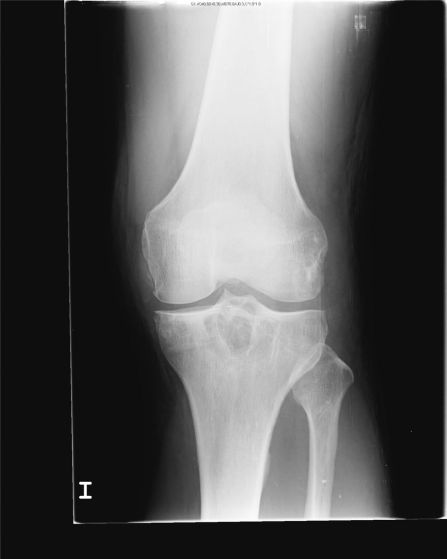

Proyección Anteroposterior de rodilla que muestra: 1) calcificación en cuña del menisco 2) calcificación en cuña siguiendo en paralelo al cóndilo femoral.

El espacio articular se encuantra conservado, nótese las radiodensidades con distribución punteada o lineal.